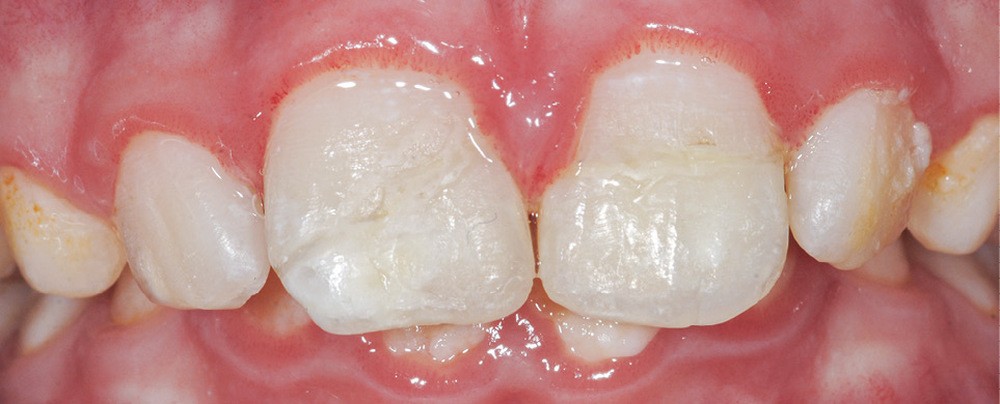

La présence d’une hypominéralisation molaire-incisive (MIH) est notée, car 16 et 36 présentent des opacités beiges et jaune brun.

La MIH se définit par la présence d’une hypominéralisation sur au moins une première molaire permanente et, éventuellement, par une hypominéralisation sur les incisives [4].

Du côté des fragments dentaires, une gorge est réalisée au niveau de la dentine afin d’aménager de la place au matériau positionné sur la dent. Les fragments sont ensuite mordancés (30 secondes pour l’émail, 15 secondes pour la dentine). Le morceau est abondamment rincé, légèrement séché à l’air doux puis tamponné avec une microbrossette neuve pour ne pas dessécher les surfaces. Un adhésif est ensuite appliqué et frotté vigoureusement sur la surface de collage du fragment puis photopolymérisé selon les conseils du fabricant. Des étapes identiques sont réalisées sur la surface de collage de la dent fracturée (mordançage, rinçage, séchage, adhésif, photopolymérisation). Afin de limiter les saignements, un cordonnet rétracteur imbibé d’un produit hémostatique tel que le sulfate d’aluminium peut être inséré dans le sulcus. Un composite fluide est appliqué sur la surface de collage du fragment dentaire qui est ensuite positionné sur la dent. Les excès sont éliminés à la microbrossette. Puis l’ensemble est photopolymérisé. Les fragments de 11 et 21 sont collés successivement (fig. 6 et 7). Les surfaces vestibulaires et linguales sont polies avec des disques pop-on (Sof-lex™, 3M) puis avec une cupule siliconée emplie de pâte diamantée (Diamond polish™, Ultradent). Une hypominéralisation est notée sur la 11, en lien avec la MIH du patient (fig. 6). Les hypominéralisations sont en effet des zones plus à risques de fractures. La prévention des conséquences de ces traumatismes par un procédé d’érosion-infiltration en profondeur est fondamentale [5]. Les propriétés mécaniques de cet émail affaibli en ressortent augmentées [6].

À 3 mois, sur la radiographie (fig. 9) l’apex semble se fermer et les tests de sensibilité sont toujours positifs. De la plaque dentaire (fig. 10) est observée. Une motivation à l’hygiène à l’aide d’un révélateur de plaque est réalisée. Par crainte, les enfants (ou les parents pour les plus jeunes) évitent fréquemment le brossage des dents traumatisées ; des gingivites peuvent être secondaires à ce défaut d’hygiène dans un contexte déjà inflammatoire consécutivement au traumatisme. Une attention particulière doit donc être portée à l’hygiène bucco-dentaire du patient.